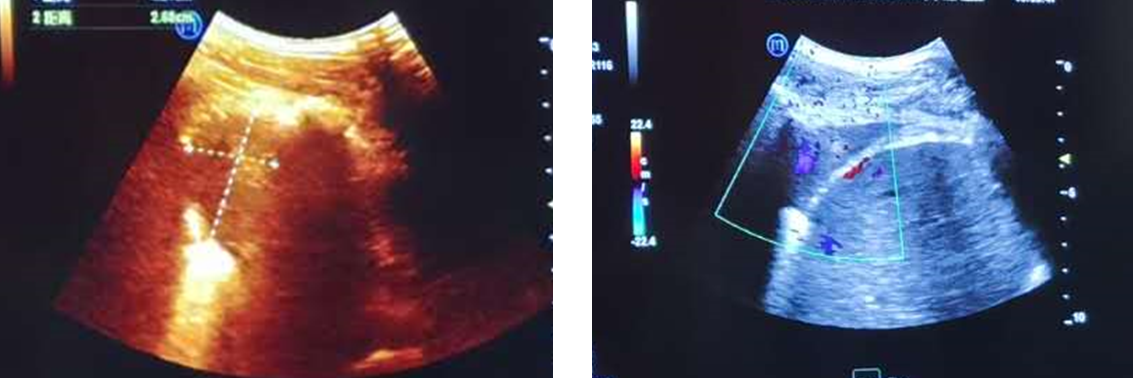

徐作峰主任紧接着为病例二患者进行远程超声检查会诊。该患者是一名65岁男性,发现胰腺、肝脏、右肺多发病灶,MDT讨论怀疑胰腺原发癌并肝脏及右肺多发转移,但是右下肺后基底段肿物不能排除是原发癌,所以建议行超声引导下右下肺肿物穿刺活检以明确病变性质。由于病灶较大并靠近胸膜和脊柱,下方临近右侧膈肌及肝脏,因此,超声有望能够显示右肺病灶,并实施超声引导下穿刺活检。患者取俯卧位趴在检查床上,徐作峰主任操纵机械臂探头先找到患者的肝脏和右侧膈肌,然后探头上移一个肋间在患者右侧背部近脊柱处扫查,再不断调整探头方向,避开肋骨干扰,直至超声能够清楚地显示右肺病灶。徐作峰主任一边操作探头,一遍为凤庆医生讲解可行的穿刺切面及穿刺路径。并交代该病灶体积较大,超声下容易穿刺,但穿刺时注意避开肋骨,要充分显示病灶最大切面。若有超声造影剂,还可以在穿刺前行超声造影检查,评估病灶是否存在液化坏死区,穿刺时需避开肿物的坏死区域,得到较好的病理样本,提高病理结果的可信度。

远程超声下显示的患者右肺病灶